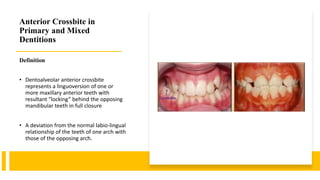

Anterior Cross-bites In Primary Mixed Dentition-pedo | PPT

www.slideshare.net

www.slideshare.net

Anterior Crossbite In Primary And Mixed Dentitions.pptx

www.slideshare.net

www.slideshare.net